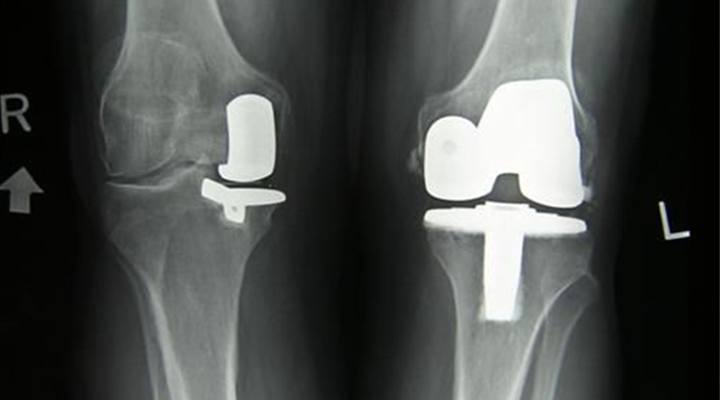

En la artroplastia de la rodilla, el cirujano extrae el hueso y el cartílago dañados del fémur, la tibia y la rótula para reemplazarlos con una articulación artificial. En la mayoría de las personas, la artroplastia de la rodilla mejora considerablemente la movilidad y alivia el dolor; pero en algunos pacientes, el dolor continúa después de la intervención quirúrgica.